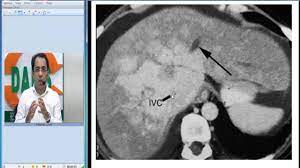

Chiasmata -mə-tə or chiasmas also chiasms 1. Esophageal varices are extremely dilated sub-mucosal veins in the lower third of the esophagus. Located in metro Denver northern Colorado and western Nebraska serving all of the Front Range our team consists of board-certified and fellowship-trained interventional radiologists. This results in hepatic congestion similar to Budd-Chiari syndrome and post-sinusoidal portal hypertension. The patients condition should be monitored throughout the procedure. They are most often a consequence of portal hypertension commonly due to cirrhosis. Toxic injury to liver sinusoids causes sloughing of endothelial cells that embolize to hepatic venules and cause eventual fibrosis of the venules. Coin in the Esophagus. There is no clear consensus regarding the number of occluded veins some authors claim that there should be at least one occluded hepatic vein 7 others state that there are no significant.

Carcinoma of the Colon. Budd-Chiari syndrome a blockage in one or more veins that carry blood from the liver back to the heart. And coumarin skin necrosis adrenal gland hemorrhage and infarction. Toxic injury to liver sinusoids causes sloughing of endothelial cells that embolize to hepatic venules and cause eventual fibrosis of the venules. Chiari malformation CM is a structural defect in the cerebellum characterized by a downward displacement of one or both cerebellar tonsils through the foramen magnum the opening at the base of the skull. Embolism and thrombosis of. La présence dune ou plusieurs affections prothrombotiques est fréquente La prise en charge repose sur un traitement anticoagulant précoce le traitement de l.